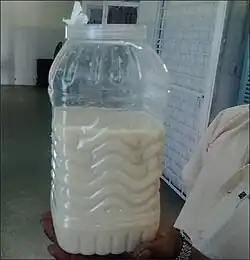

| Urine from a patient with filarial chyluria. | |

Chyluria, also called chylous urine, is a medical condition involving the presence of chyle in the urine stream,[1] which results in urine appearing milky white.[2] The condition is usually classified as being either parasitic or non parasitic. It is a condition that is more prevalent among people of Africa and the Indian subcontinent.

Once the lymph channels are blocked, one may open into the kidney hilum or ureter or sometimes into the bladder and chyle can leak into the urinary tract resulting in milky white urine. Blood sometimes mixes with the urine resulting in haemato-chyluria.